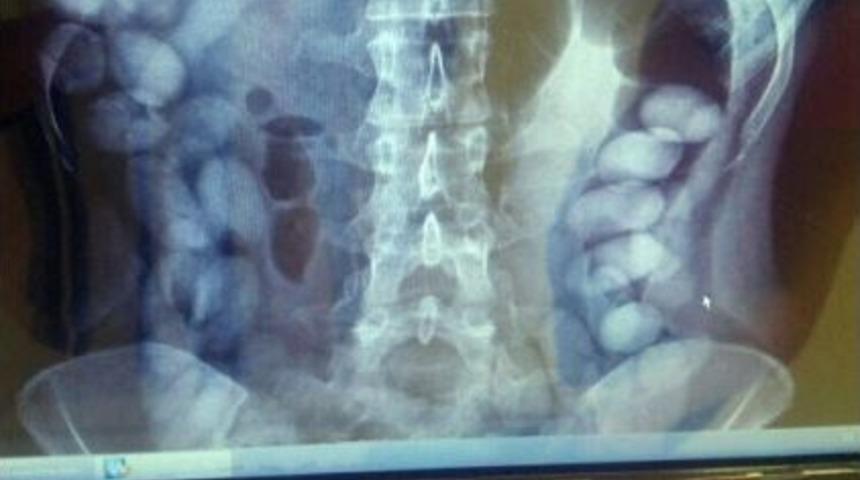

Antalya Havalimanı’nda Venezuela uyruklu uyuşturucu kuryesi kadının sindirim sisteminden 78 kapsül kokain çıkarıldı. Sindirim sistemindeki kokain kapsülleri, çekilen röntgen filmiyle ortaya çıkarıldı.Edinilen bilgiye göre, Antalya Emniyet Müdürlüğü Narkotik Suçlarla Mücadele Şube Müdürlüğü ekipleri, 2 gün önce Zürih-Antalya seferini yapan uçakla kente uyuşturucu madde getirileceği bilgisi üzerine harekete geçti. Daha önceden uyuşturucunun ya valiz yada şahsın vücudunda getirileceği bilgisine ulaşan ekipler Venezuela uyruklu M.S.B.R.’yi (29) uçaktan indiği esnada gözaltına aldı. Şüphelinin uyuşturucu maddeleri kapsül halinde yutmuş olabileceğini değerlendiren polis adlıkları kararla, şüpheliyi hastaneye götürdü. Hastanede sindirim sistemi röntgen filmi ile kontrol edilen şüphelinin midesinde kokain olduğu değerlendirilen her biri 10-12 gram ağırlığında 78 kapsül ortaya çıktı. Şüpheliden doğal yollarla 71 kapsülün çıkarıldığı belirtildi.Venezuela uyruklu şüpheli kadın hakkında "Uluslararası Uyuşturucu Madde Ticareti Yapmak" suçundan işlem yapılacağı bildirildi.